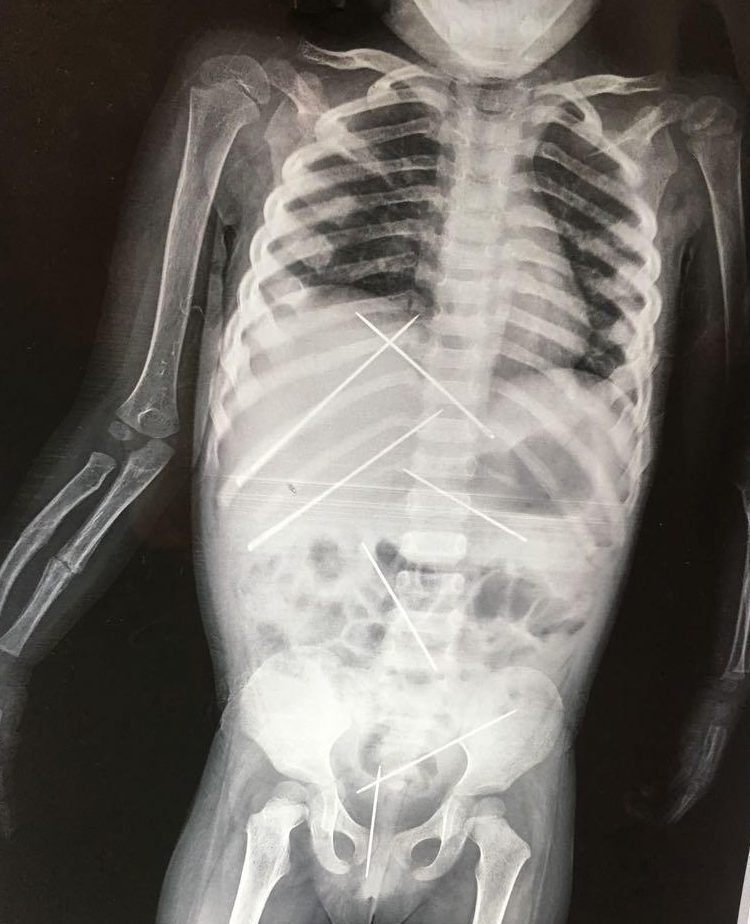

Σοκάρει η υπόθεση με ένα τρίχρονο κοριτσάκι στην Ινδία όπου είχε μέσα στο κορμάκι του σχεδόν 10 βελόνες, οι οποίες είχαν χρησιμοποιηθεί πάνω του σε τελετές μαύρης μαγείας.

Όταν υποβλήθηκε σε ακτινογραφία, οι γιατροί αντίκρισαν ένα πρωτοφανές θέαμα.

Σχεδόν 10 μεγάλες βελόνες είχαν καρφωθεί μέσα στο σώμα του 3χρονου κοριτσιού, σε διάφορα σημεία. Επίσης, το ένα χέρι του παιδιού ήταν σπασμένο.

Το 3χρονο κορίτσι υποβλήθηκε σε εγχείρηση και της αφαιρέθηκαν οι βελόνες μέσα από το σώμα της.